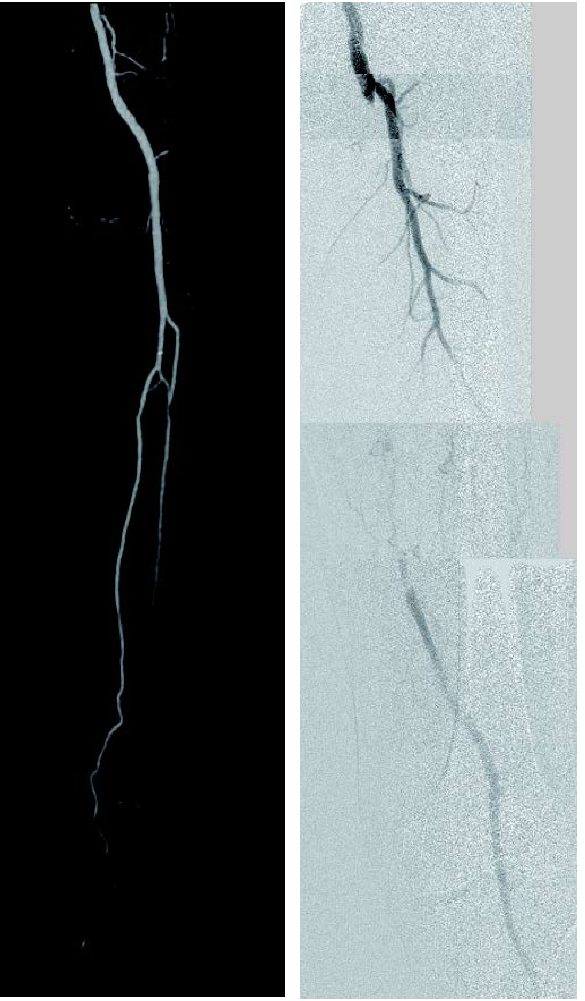

- 対象病変部位(図1): 左 SFA 閉塞(病変長約22 cm)

図1:術前